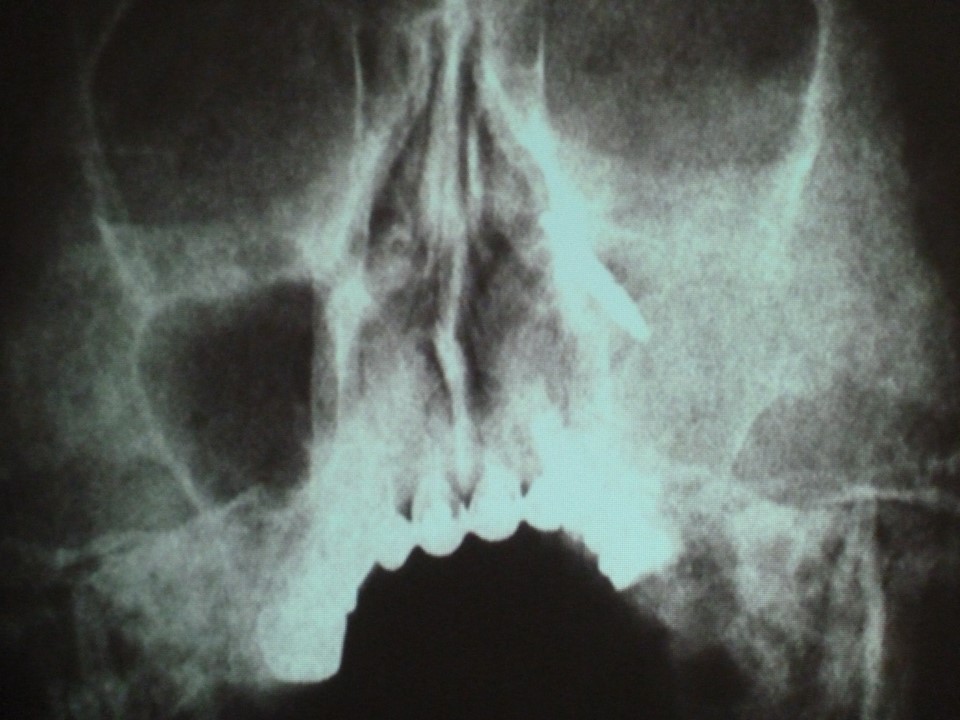

Fotoreportaż Kirgistan 2015 Obejrzyj film Ta przeglądarka nie obsługuje HTML5 video.Fotorelację przygotował dr Tomasz Grotowski poprzedni artykuł następny artykuł Ocena książki Rzadki przypadek bocznego obrzęku twarzy